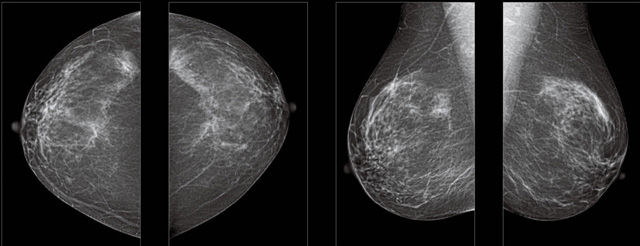

首先不同年齡階段的乳腺篩查頻次種類不一樣。青春期女性第二性征明顯發(fā)育開始,每個月進(jìn)行自我乳腺檢查。20-30歲的女性就不推薦進(jìn)行乳腺檢查,因?yàn)槟贻p女性的乳腺組織非常緊急。鉬靶X光線等檢查的射線不能辨別腫塊跟腺體。身體就白吸收了輻射,影響了身體健康。每個月自檢一次就是在洗澡時候,對著鏡子看看乳房外觀正常,皮膚潰爛、腫塊、顏色改變、再摸一下有沒小疙瘩。乳腺高危人群,特別是有乳腺CA遺傳傾向的女性,乳腺導(dǎo)管跟小葉不典型增生,原位癌。30歲前有乳房放療的女性。乳腺癌篩查可以把年齡提前到40歲前。40到70歲的女性可以在適合的機(jī)會篩查。

采用影像檢查技術(shù)來發(fā)現(xiàn)疑似特定病檢查跟人群的普查。一到兩年進(jìn)行一次X光線的乳腺檢查。記過是C或者D型,可以加上B超協(xié)同。還可以一年一次核磁共振MRI檢查。70歲以上的女性認(rèn)為絕經(jīng)的女性是比較安全的。實(shí)際上也有乳腺癌的風(fēng)險(xiǎn)。65歲以上風(fēng)險(xiǎn)也很大。也是需要進(jìn)行機(jī)會性篩查。